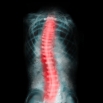

Spinal Decompression Traction

Spinal decompression therapy is a non-surgical treatment for back pain that involves stretching the spine to relieve pressure on the discs and nerves. The treatment is designed to create negative pressure in the spine, which can help to reposition bulging or herniated discs, reduce inflammation, and promote healing in the affected area.

Spinal decompression therapy works by creating negative pressure within the spine, which can help to reposition bulging or herniated discs, reduce inflammation, and promote healing in the affected area. The negative pressure created during the treatment can also help to increase blood flow to the affected area, which can aid in the healing process.